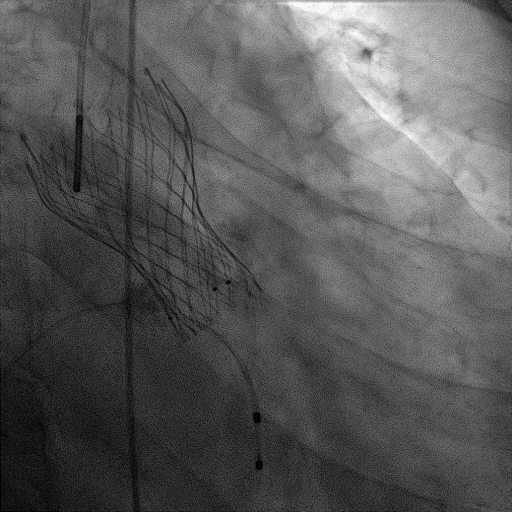

主动脉根部造影

18mm球囊预扩张

23mm瓣膜精准定位

瓣膜+Chimney支架释放

瓣膜形态良好,结果满意